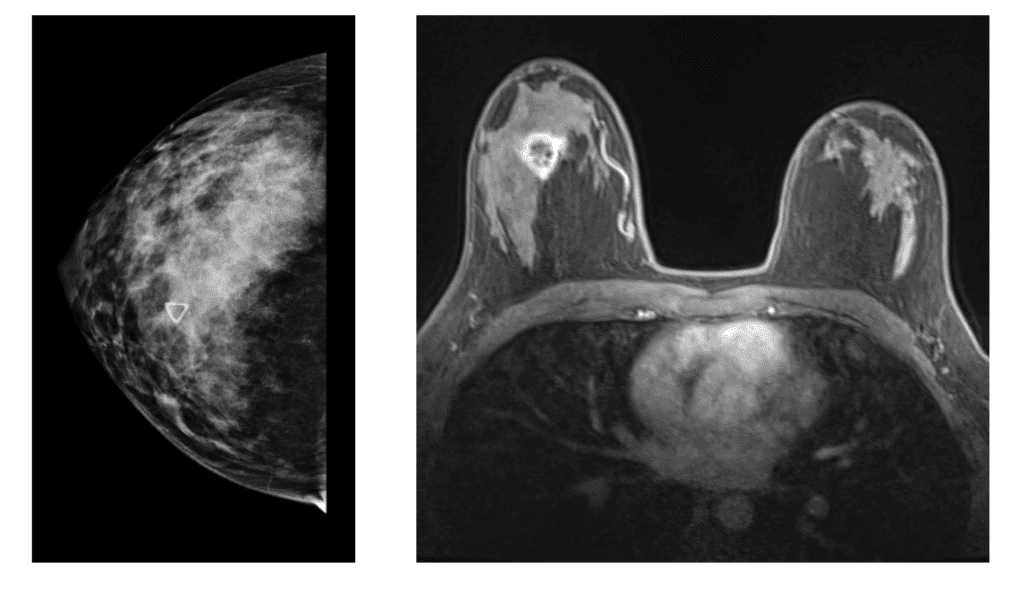

Patient six months postpartum with new lump right breast that was not well visualized on mammogram but appeared distinctly on MRI.